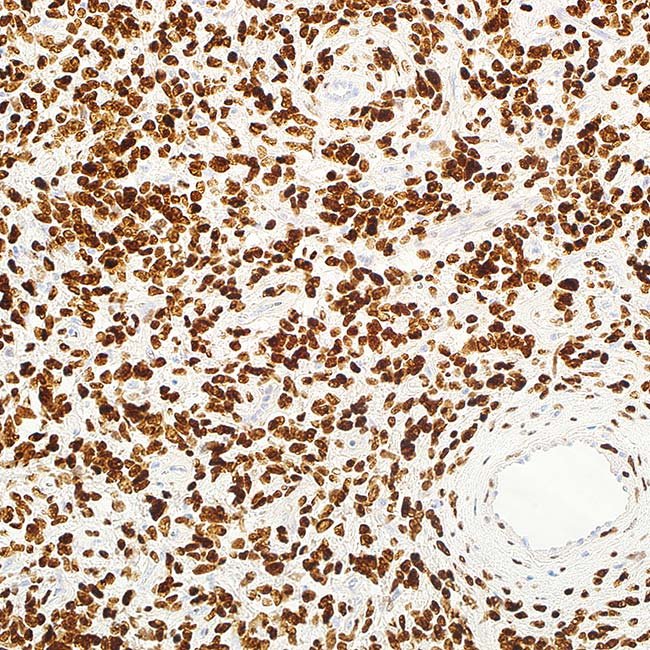

STAT6 (EP325)

A rabbit monoclonal antibody for immunohistochemistry iscalled STAT6. The gene STAT6 is human. This gene encodesa protein that belongs to the STAT transcription factorfamily. Receptor-associated kinases phosphorylatemembers of the STAT family in response to cytokines andgrowth factors. These members subsequently form homo-or heterodimers and go into the cell nucleus, where theyfunction as transcription activators. This protein is essentialfor triggering biological reactions mediated by IL4. It hasbeen discovered to stimulate the expression ofBCL2L1/BCL-X(L), which is in charge of IL4’s anti-apoptoticproperties. IHC can detect STAT6 protein expression in thenucleus and cytoplasm of many tissues. Solitary fibroustumours (SFT) have been found to exhibit recurrentsomatic fusions of the NGFI-A–binding protein 2 (NAB2)and STAT6 genes, which are situated at chromosomalregion 12q13. In one investigation, nuclear expression ofthe STAT6 antibody, which is typically diffuse and strong,was found in 59% of 60 SFT cases. With the exception ofone deep fibrous histiocytoma and three dedifferentiatedliposarcomas, which displayed mild staining, all othertumour types of soft tumour tissues tested negative forSTAT6. A very sensitive and specific immunohistochemicalmarker for SFT, the STAT6 antibody can be used todifferentiate this tumour type from histologic imitators. Asubset of dedifferentiated liposarcoma has STAT6amplified, which results in STAT6 protein expression thatcan be identified by immunohistochemistry. This could bea problem when trying to discriminate between solitaryfibrous tumour and dedifferentiated liposarcoma. Theseresults demonstrate the genomic complexity andheterogeneity of dedifferentiated liposarcomas and pointto a potential role for STAT6-mediated transcriptionalactivity in certain cases of the disease.

ControlSolitary Fibrous Tumor